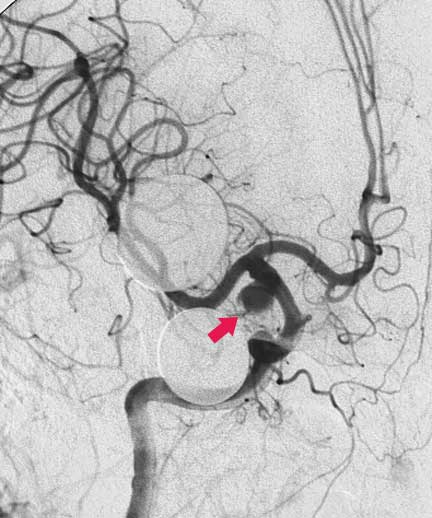

CASO 3 : Embolización endovascular con microespiras (coils) en paciente con hemorragia cerebral resultando en cefalea y trastorno de la conciencia

Antes de la embolización

Despuès de la embolización. Note cierre del aneurisma conservando las arteriias sanas. La paciente se recuperó completamente.